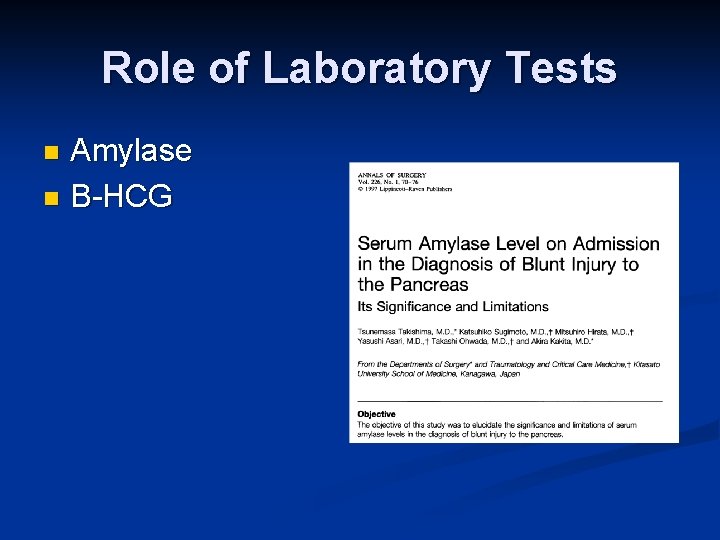

Role of Laboratory Tests Amylase n B-HCG n